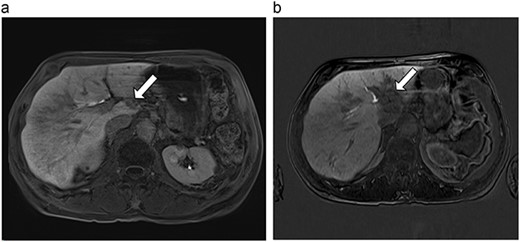

| 3 (5a,b) | 68, F | Colon adenocarcinoma | 6 cycles modified FOLFOX-6 | 8 | Laparoscopic microwave ablation and low anterior resection of colon | 5 | 36.2 | 31.2 | 15 | No |

(a) Pre-ablation MRI demonstrating 5 mm lesion in caudate lobe of liver. (b) Post-ablation MRI (19 days postoperatively) demonstrating 36.2 mm complete ablation of caudate lesion.